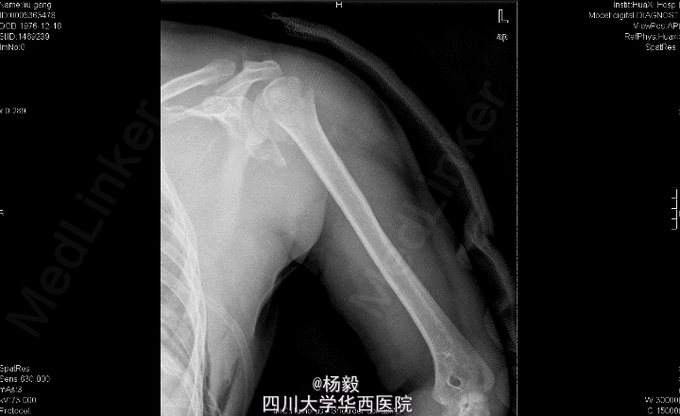

男,33岁11月,因“车祸伤后全身多处疼痛、左上肢活动障碍9小时”入院。 患者自述入院前9小时,被货车撞伤,具体受伤姿势及着力方式不清,患者原发昏迷约5分钟,醒后能回忆受伤情况,患者述胸部及左肩部疼痛,呼吸困难,气促,左上肢感觉麻木,左手伸屈活动受限,患者无恶心呕吐,无咯血,感腹部稍微疼痛,无大小便失禁,其余四肢无活动障碍,曾经当地医院诊治,具体诊断不详,行对症治疗后,患者感呼吸困难加重,为进一步治疗,患者转我院,门诊请胸科会诊后行左侧胸腔闭式引流术,请普外科会诊后,认为腹部无明显指征,暂观察,急诊以“左肩胛骨骨折,左肱骨外科颈骨折,胸腔积液'收住我科。

胸廓左侧胸廓呼吸动度减弱,左胸部腋中线处见一闭式引流管接水封瓶。,双肺叩诊呈清音,双肺呼吸音清,未闻及干湿啰音及胸膜摩擦音。腹部外形正常,全腹柔软,上腹压痛,无反跳痛,腹部未触及包块,肝脏肋下未触及,脾脏肋下未触及,双肾未触及。双下肢无水肿。专科检查:视:左上臂夹板外固定,解开夹板后见左肩部及左上臂肿胀,左上臂下段外侧见约5cm*8cm皮肤擦伤。触:左肩胛部及左肩部压痛,左前臂下段 以远痛温触觉较对侧减退,左桡动脉能扪及,左手甲床微循环正常。动量:左肩关节、左肘关节、左腕关节及左手指各关节伸屈活动受限。 辅助检查:X片检查示:左肩胛骨及左肱骨上段骨折,左侧多发肋骨骨折,左肺挫伤,左胸腔积液,脾区高密度影。

初步诊断:1、左肩胛骨粉碎性骨折。2、左肱骨外科颈骨折伴神经损伤。3、左侧胸腔积液闭式引流术后。4、左侧多发肋骨骨折。5、左肺挫伤。6、脾脾脏损伤? 全麻下行左肱骨外科颈骨折切开复位内固定术。